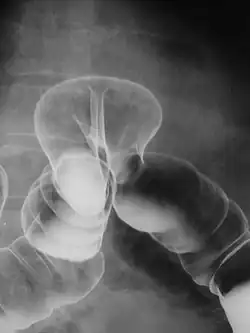

Un lavement opaque radiologique (dit lavement baryté) peut être effectué pour révéler la dilatation du côlon ou de l’intestin grêle au-dessus d’une zone rétrécie. Ce test est utilisé chez les nouveau-nés qui sont incapables d’évacuer les selles. Pour cela le médecin introduit dans le côlon un liquide contenant du baryum, via l'anus. Ceci permet d'observer l'intestin aux rayons X. Ce test est aussi utile chez les enfants afin de déterminer sur quelle longueur le côlon est affecté.